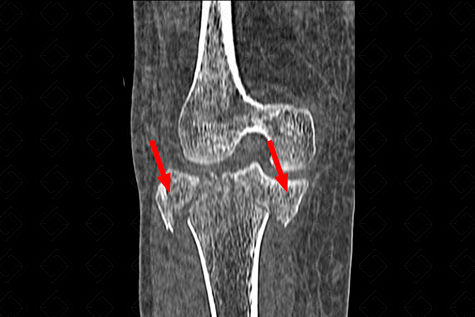

Texto alternativo para a imagem Figura 2. Créditos: Dra. Elazir Mota - Rio de Janeiro/RJ

Descrição das f iguras 2 e 3: Tomografia computadorizada do joelho direito. Fratura do platô tibial bicondiliana (ou seja, envolve os dois côndilos tibiais - setas vermelhas), Schatzker tipo V . [cms-watermark]